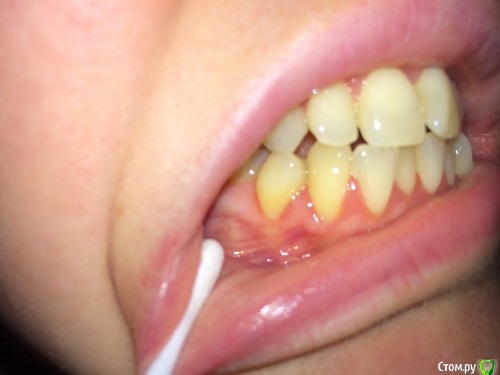

lalafa Опубликовано 16 августа, 2017 Поделиться Опубликовано 16 августа, 2017 (изменено) Здравствуйте, помогите, пожалуйста, советами.Мне 29 лет. Хронические заболевания - гранулезный фарингит, гастрит, ГЭРБ, сколиоз. У меня генерализованная рецессия десны, катаральный гингивит, пародонтальных карманов нет. Рекомендовано ортодонтическое лечение. НО ортодонты предупредили, что велика вероятность продолжения рецессии десны во время лечения и ухудшения ситуации. Посетила 2 пародонтологов, мнения противоположные. Один рекомендует операцию по закрытию рецессии методом пересадки трансплантата с неба. Хочет оперировать до ортодонт лечения самые проблемные зубы - клыки на нижней челюсти и 4ку. Мотив - утолщить десну, чтобы она выдержала брекеты и не рецессировала еще больше.Другой пародонтолог говорит, что так как именно эти зубы "не стоят в зубной дуге" (цитата врача) трансплантат с неба не приживется и результата не будет. Советует делать операцию после снятия брекетов на прямые зубы.Вопросы:1) Насколько в принципе опасно при такой рецессии проводить ортодонтическое лечение? зубы могут расшатываться и выпасть в процессе лечения?2) Закрывать рецессию до брекетов или после? Действительно, на таких вывернутых зубах не приживается трансплантат?3) Постоянно мучаюсь с катаральным гингивитом. Прохожу Проф чистку раз в 6 месяцев, но без толку. за чистотой слежу и самостоятельно, но скученные зубные ряды все равно провоцируют гингивит. Можно надеяться, что после брекетов гингивит вылечится? Изменено 16 августа, 2017 пользователем lalafa Ссылка на комментарий

lalafa Опубликовано 17 августа, 2017 Автор Поделиться Опубликовано 17 августа, 2017 Про гигиену чищу зубы как показал стоматолог, по схеме.Нитью больно пользоваться, потому что сильная скученность.После проф чистки гингивит все равно есть, просто десны не кровоточат, но они красные и припухшие. фото сделаны после недели применения ополаскивателя, от которого сильно желтеют зубы, поэтому такой вид, как будто проблемы с гигиеной.Скажите. пожалуйста, на снимке есть признаки пародонтоза? Ссылка на комментарий

Art 7 Опубликовано 17 августа, 2017 Поделиться Опубликовано 17 августа, 2017 ополоскиватель не окрашивает зубы, он окрашивает налёт. пластику до брекетов, вы не первая со скученностью, есть и сложнее ситуации когда пациенты справляются. породонтоза у вас нет Ссылка на комментарий

drusmanov Опубликовано 11 октября, 2017 Поделиться Опубликовано 11 октября, 2017 в вашей ситуации нужно уделять больше времени гигиене, пока процесс не стабилизируется, проведение пластики мягкими тканями может быть очень рискованным. после стабилизации уже проводить закрытие рецессий. в каких объёмах её проводить надо смотреть по кт совсестно с ортодонтом, когда у ортрдонта есть понимание куда будут двигаться зубы пациентка тут уже не сможет самостоятельно чистить Ссылка на комментарий